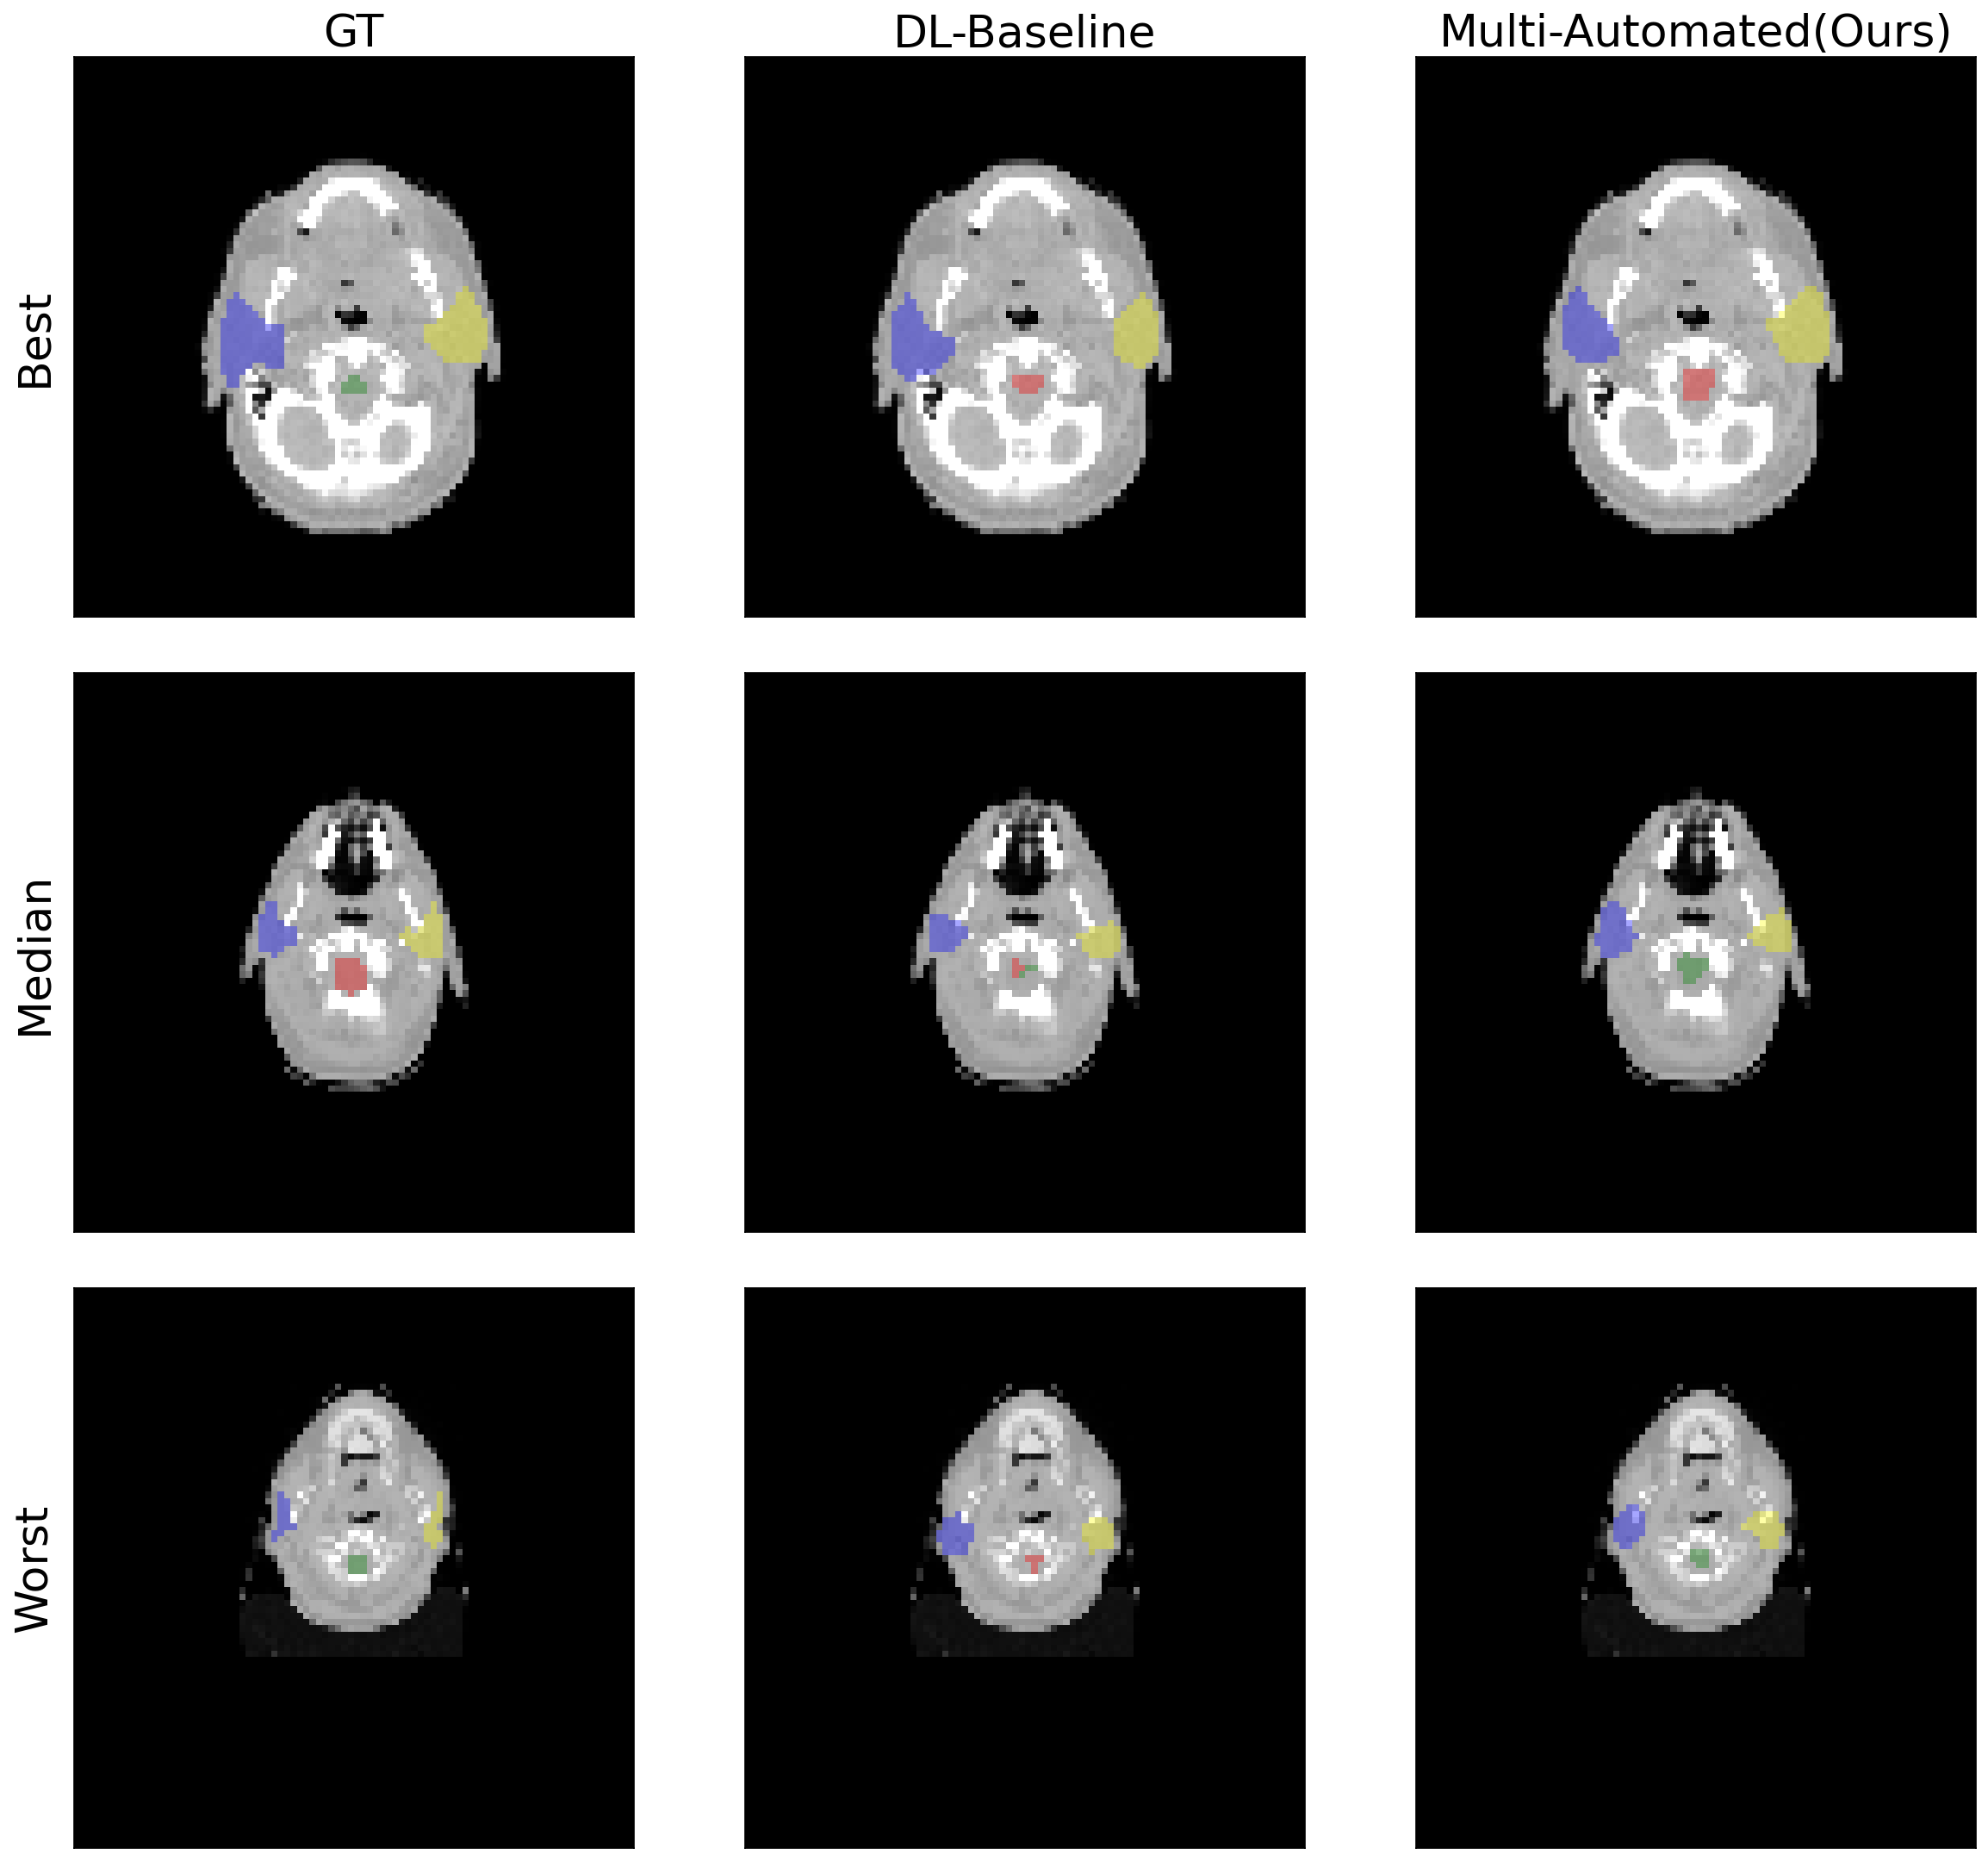

Additionally, results in Table 4 and Table 5 show that Multi-Automated achieves comparable performance in contouring when trained for dose prediction simultaneously. The Dice Score Coefficients for the baseline single-task learning model for contouring are 0.818 and 0.674 for the prostate and OpenKBP datasets, respectively. In contrast, Multi-Automated achieves dice score coefficients of 0.824 and 0.716, respectively, showing better performance in OpenKBP datasets. For Hausdorff distance, compared to 7.549 and 39.831 in baseline, Multi-Automated results show 12.049 and 22.872 for Prostate and OpenKBP datasets, respectively. In Figure 3 and Figure 5, we further illustrate the qualitative results of both the baseline model and Multi-Automated for the prostate and OpenKBP datasets, respectively.

Table 5: Dice score coefficient and Hausdorff distance using OpenKBP dataset for both DL contouring models: baseline (DL-Baseline) and the automated contouring and planning model using multi-task learning (Multi-Automated). Better results for each ROI and each metric are bolded. Higher the better for dice score coeffcient, denoted as \uparrow, lower the better for Hausdorff distance, denoted as \downarrow. \dagger Denotes significant differences (p <<< 0.5) in either contouring metric compared to baseline, determined through paired t-tests and Bonferroni correction.

ROIs Dice score coefficient(\uparrow) Hausdorff Distance (\downarrow)

DL-Baseline Multi-Automated DL-Baseline Multi-Automated

Brain stem 0.717 0.750superscript0.750\textbf{0.750}^{\dagger}0.750 start_POSTSUPERSCRIPT † end_POSTSUPERSCRIPT 46.103 22.073superscript22.073\textbf{22.073}^{\dagger}22.073 start_POSTSUPERSCRIPT † end_POSTSUPERSCRIPT

Spinal cord 0.628 0.716superscript0.716\textbf{0.716}^{\dagger}0.716 start_POSTSUPERSCRIPT † end_POSTSUPERSCRIPT 13.981 16.002

Left parotid 0.673 0.693superscript0.693\textbf{0.693}^{\dagger}0.693 start_POSTSUPERSCRIPT † end_POSTSUPERSCRIPT 44.679 30.106superscript30.106\textbf{30.106}^{\dagger}30.106 start_POSTSUPERSCRIPT † end_POSTSUPERSCRIPT

Right parotid 0.680 0.704superscript0.704\textbf{0.704}^{\dagger}0.704 start_POSTSUPERSCRIPT † end_POSTSUPERSCRIPT 54.563 23.308superscript23.308\textbf{23.308}^{\dagger}23.308 start_POSTSUPERSCRIPT † end_POSTSUPERSCRIPT

Average 0.674 0.716 39.831 22.872

Figure 5: In this figure, we present the results of DL automated contouring using OpenKBP dataset. The image showcases the ground truth labels (GT), and the automated contouring outputs from the baseline (DL-Baseline) and the automated contouring and planning model using multi-task learning (Multi-Automated). Additionally, we provide the Dice Score Coefficient for the segmentation output. The figure includes representative examples, displaying the best, median, and worst cases from our test dataset.